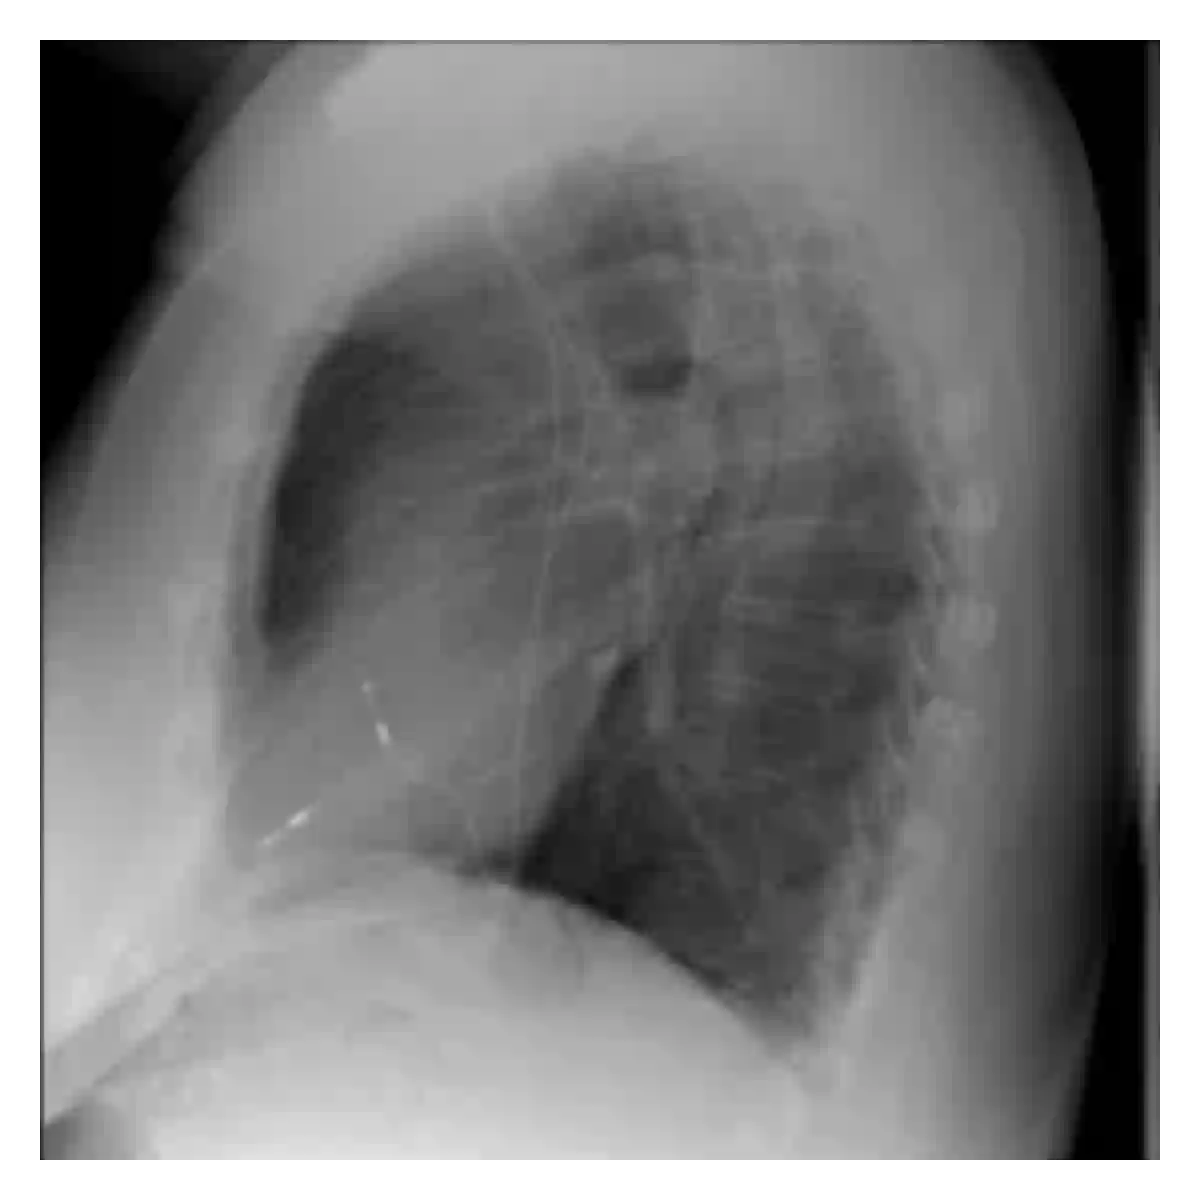

The evaluation of infectious disease processes on radiologic images is an important and challenging task in medical image analysis. Pulmonary infections can often be best imaged and evaluated through computed tomography (CT) scans, which are often not available in low-resource environments and difficult to obtain for critically ill patients. On the other hand, X-ray, a different type of imaging procedure, is inexpensive, often available at the bedside and more widely available, but offers a simpler, two dimensional image. We show that by relying on a model that learns to generate CT images from X-rays synthetically, we can improve the automatic disease classification accuracy and provide clinicians with a different look at the pulmonary disease process. Specifically, we investigate Tuberculosis (TB), a deadly bacterial infectious disease that predominantly affects the lungs, but also other organ systems. We show that relying on synthetically generated CT improves TB identification by 7.50% and distinguishes TB properties up to 12.16% better than the X-ray baseline.